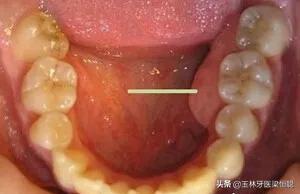

2.對于生理性的骨隆突,一般也不進(jìn)行調(diào)節(jié)。在第三磨牙和雙尖牙舌側(cè)牙槽骨的舌側(cè)骨隆突、上頜骨骨隆突、下頜隆突等生理性突起,在進(jìn)行活動(dòng)義齒修復(fù)時(shí)應(yīng)避開這些地方,以免義齒佩戴后產(chǎn)生壓痛。